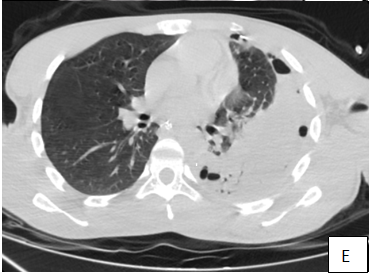

Then the patient was shifted for a computed tomography (CT) of thorax and abdomen (Figure1) which showed herniation in the left lower lung zone of the bowel loops through the disrupted left hemi diaphragm, with multiple air fluid levels. The herniated abdominal contents are positioned against the posterior wall of the thorax (dependent viscera sign).The collar at the base of the herniated bowel is more difficult to detect on the axial CT image than on reformatted images in other planes. Default of enhancement of the wall signs the ischemia. Diagnosis of complicated diaphragmatic hernia was made. Emergency surgery was decided with reduction of the hernia, Segmental colic resection. The patient was extubated and hospitalized. On follow-up, vital signs were stable and radiological examination was normal (Figure 2). The patient was discharged on the third day postoperatively.

Figure 1 A.B(axial); C(Sag):CT scan shows a left hydropneumothorax, and collapse of the left lung, contralateral shift of the mediastinal contents under tension and left anterior diaphragmatic rupture (B.arrow)with herniated perforated colon(C.arrow), D: (arrow)The nasogastric tube lying just below the cardia (stomach is not involved in the hernia) E: CT in a lung window shows air next to herniated perforated colon.